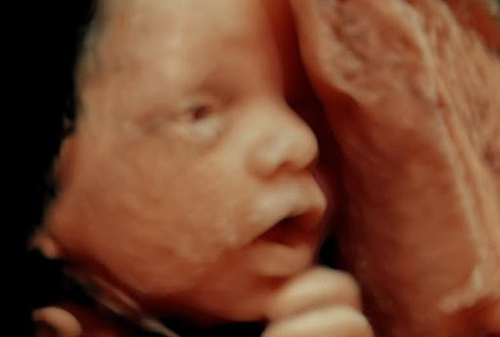

Հղիության 33-րդ շաբաթ. morevmankan.am

Եվ այսպես, մինչև փոքրիկի հետ երկար սպասվող հանդիպումը մնացել է մոտավորապես մեկ ամիս: Ի՞նչ է կատարվում հղիության 33-րդ շաբաթում:

Երեխան արագ աճում և քաշ է ավելացնում, բայց նրա ակտիվությունը նվազում է, քանի որ տարածությունը չի հերիքում:

ՊՏՂԻ ԶԱՐԳԱՑՈՒՄԸ

Երեխան կշտում է մոտավորապես 2 կգ, հասակը՝ գրեթե 44 սմ է: Շարունակում են զարգանալ թոքերը, լյարդում ձևավորվում են բշտերը:

Ակտիվորեն աշխատում է ենթաստամոքսային գեղձը. այժմ այն կարող է փոքրիկի օրգանիզմը ապահովել ինսուլինով, որն անհրաժեշտ է նորմալ նյութափոխանակության համար: Պրակտիկորեն ավարտված են փոքրիկի սրտի, էնդոկրին, իմուն, կենտրոնական նյարդային համակարգերի ձևավորումը: